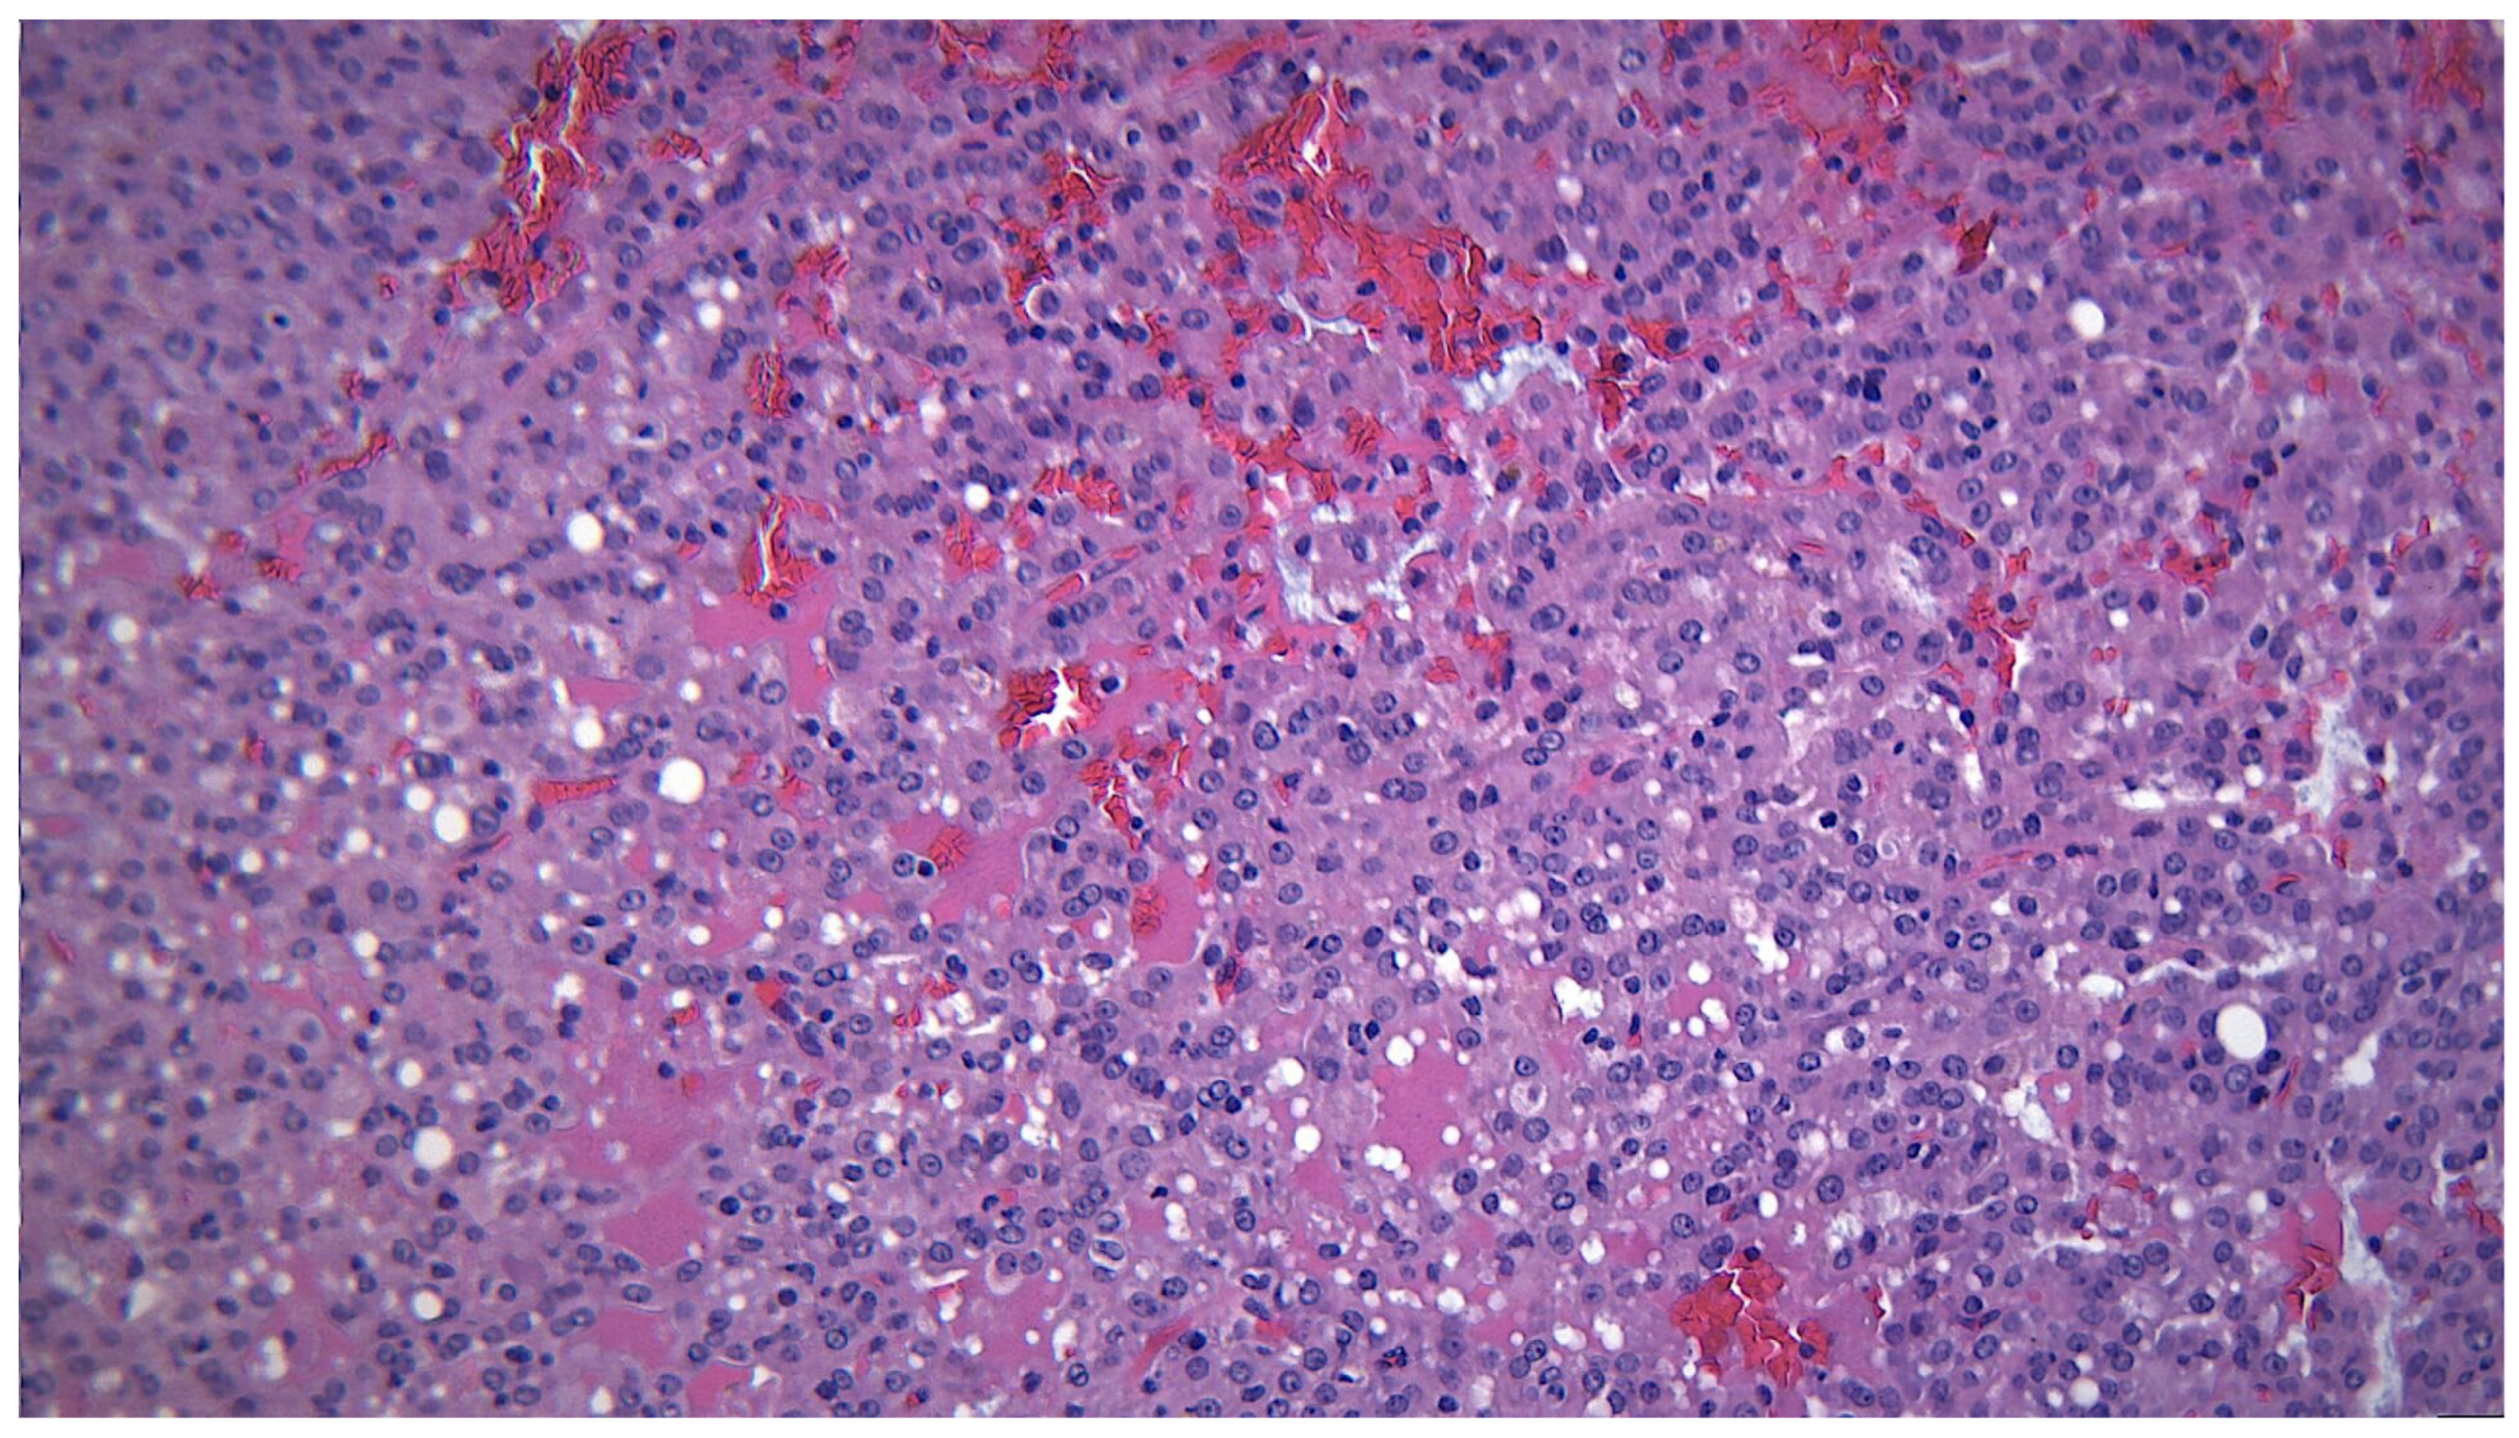

3.1. Warthin Tumor

3.5. Granulomatous Pathology